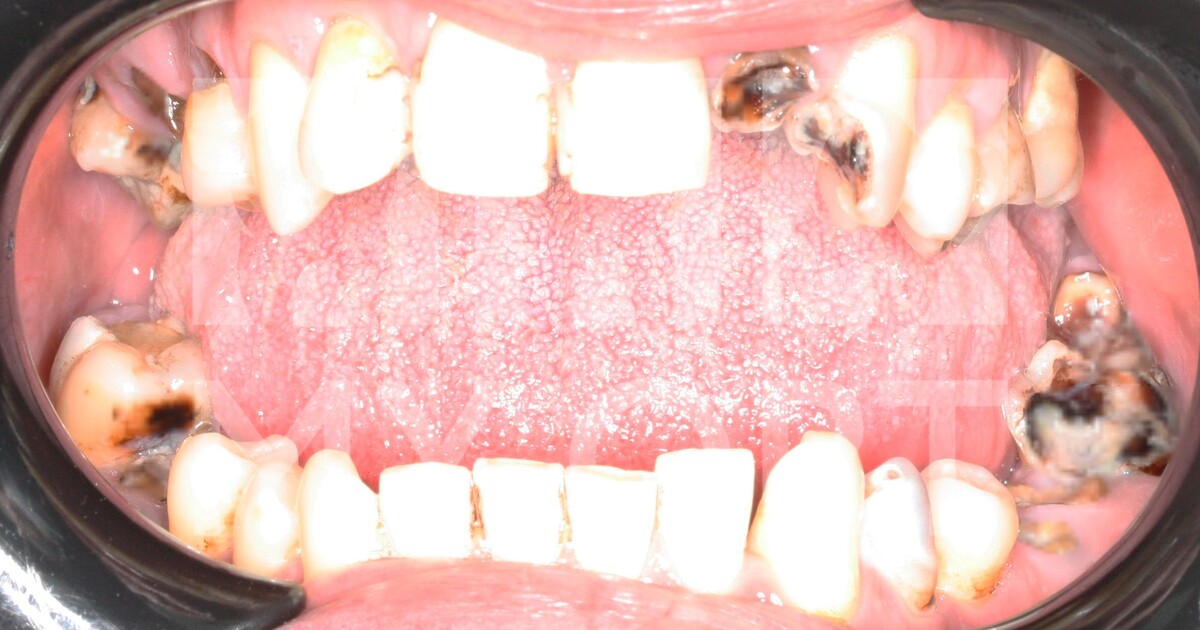

При осмотре полости рта и проведении полной диагностики были определены множественные корни разрушенных зубов, не подлежащих восстановлению.

ДО лечения:

-9